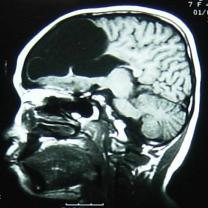

核磁检查:右侧大脑半球皮层大部分呈长T1、长T2信号,其中右额部为与脑脊液信号相同的囊性病变,与右侧脑室相沟通,右侧脑室扩大,左侧脑室大小正常,中线结构居中。MRI诊断:右侧额颞顶枕叶脑软化,右侧脑室穿通畸形(图2)。

图2 MRI显示右侧大脑半球大部分呈长T1、长T2信号,右额部为与脑脊液信号相同的囊性病变,与右侧脑室相沟通,右侧脑室扩大,左侧脑室大小正常,中线结构居中。